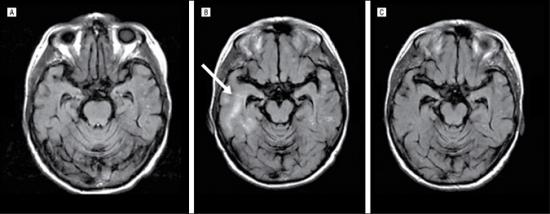

如图所示,A为对照组,B为治疗中,C为治疗后,从这组MRI扫描图可以看出,淀粉样蛋白被清除。

Sixteen patients with end-of-treatment positron emission tomographic scans were included in the analysis. The mean (95% CI) percent change from baseline difference relative to placebo (n = 4) in cortical brain amyloid level was –15.6% (95% CI, –42.7 to 11.6) for the 60-mg group (n = 6) and –35.7% (95% CI, –63.5 to –7.9) for the 200-mg group (n = 6). Two patients in the 200-mg group showed transient and focal areas of inflammation or vasogenic edema on magnetic resonance imaging scans at sites with the highest level of amyloid reduction. Gantenerumab induced phagocytosis of human amyloid in a dose-dependent manner ex vivo.